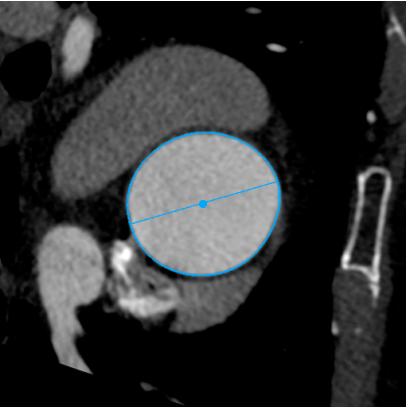

LVOT

长径: 24.3 mm

周长: 66.3 mm

面积: 321.7 mm²

RCA

下缘高度 10.2mm

上缘高度 11.9mm

瓣叶长度 12.7mm